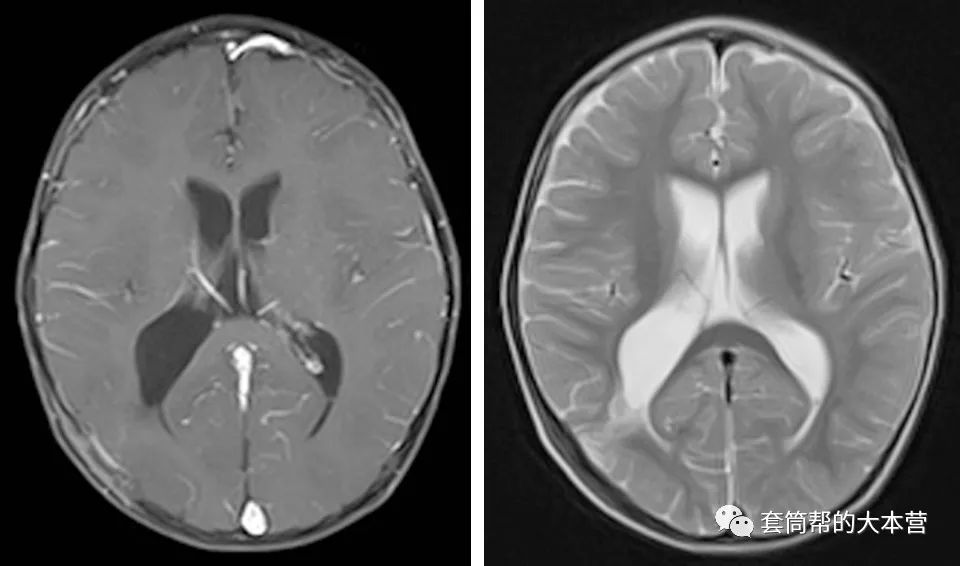

术后一个月,小宝宝回院复查。头颅磁共振证实了肿瘤全切除,而且手术的通道回弹很好,已经变得很窄,没有发生常规开颅手术时常见的脑穿通畸形。

术后一个月复查,手术通道很窄,无脑穿通畸形